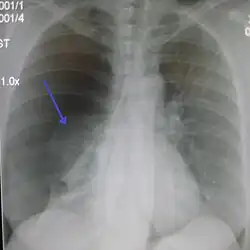

Chest X-ray

A plain chest radiograph, ideally with the X-ray beams being projected from the back (posteroanterior, or "PA"), and during maximal inspiration (holding one's breath), is the most appropriate first investigation.[35] It is not believed that routinely taking images during expiration would confer any benefit.[36] Still, they may be useful in the detection of a pneumothorax when clinical suspicion is high but yet an inspiratory radiograph appears normal.[37] Also, if the PA X-ray does not show a pneumothorax but there is a strong suspicion of one, lateral X-rays (with beams projecting from the side) may be performed, but this is not routine practice.[18][22]

It is not unusual for the mediastinum (the structure between the lungs that contains the heart, great blood vessels, and large airways) to be shifted away from the affected lung due to the pressure differences. This is not equivalent to a tension pneumothorax, which is determined mainly by the constellation of symptoms, hypoxia, and shock.[16]

The size of the pneumothorax (i.e. the volume of air in the pleural space) can be determined with a reasonable degree of accuracy by measuring the distance between the chest wall and the lung. This is relevant to treatment, as smaller pneumothoraces may be managed differently. An air rim of 2 cm means that the pneumothorax occupies about 50% of the hemithorax.[18] British professional guidelines have traditionally stated that the measurement should be performed at the level of the hilum (where blood vessels and airways enter the lung) with 2 cm as the cutoff,[18] while American guidelines state that the measurement should be done at the apex (top) of the lung with 3 cm differentiating between a "small" and a "large" pneumothorax.[38] The latter method may overestimate the size of a pneumothorax if it is located mainly at the apex, which is a common occurrence.[18] The various methods correlate poorly but are the best easily available ways of estimating pneumothorax size.[18][22] CT scanning (see below) can provide a more accurate determination of the size of the pneumothorax, but its routine use in this setting is not recommended.[38]

Not all pneumothoraces are uniform; some only form a pocket of air in a particular place in the chest.[18] Small amounts of fluid may be noted on the chest X-ray (hydropneumothorax); this may be blood (hemopneumothorax).[16] In some cases, the only significant abnormality may be the "deep sulcus sign", in which the normally small space between the chest wall and the diaphragm appears enlarged due to the abnormal presence of fluid.[19]